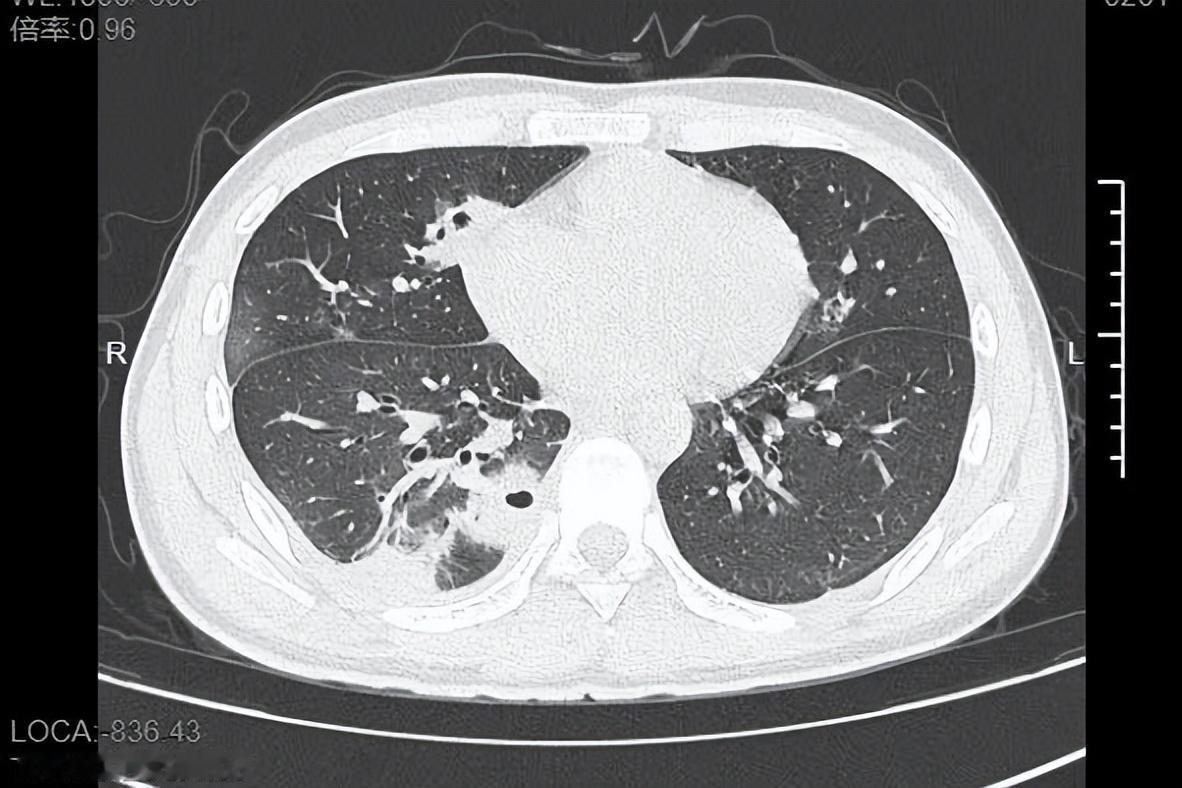

熬到第三天,小林体温飙至39℃,赶紧就医。CT检查结果让医生都皱眉:他的肺里布满了十几个空洞,部分肺组织已经坏死,确诊为血源性肺脓肿!细菌培养显示,罪魁祸首是“金黄色葡萄球菌”——这种藏在每个人皮肤表面的细菌,竟顺着挤痘的伤口闯进了血液,一路侵袭到肺部。